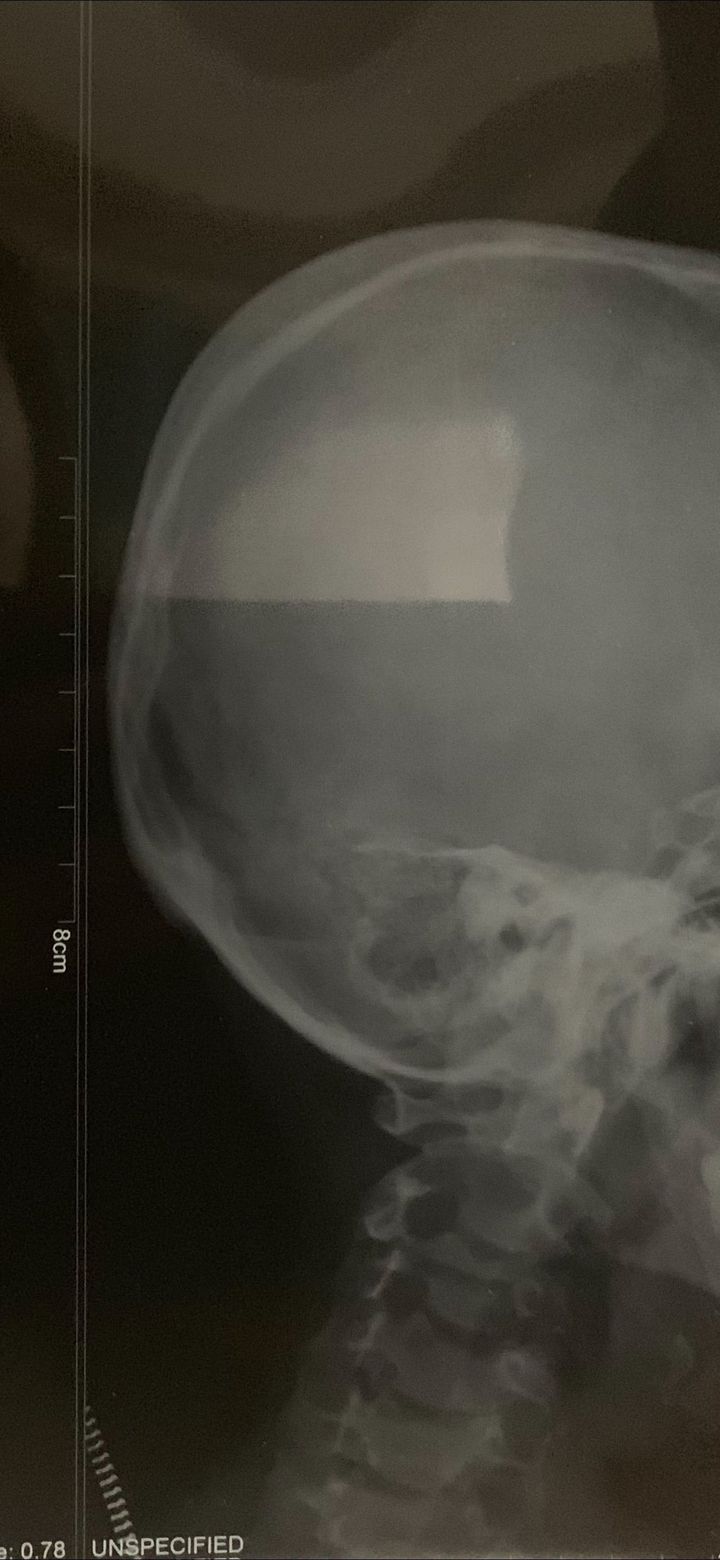

X-ray

I want to ask if this is normal or not because there’s swollen on back of the skull